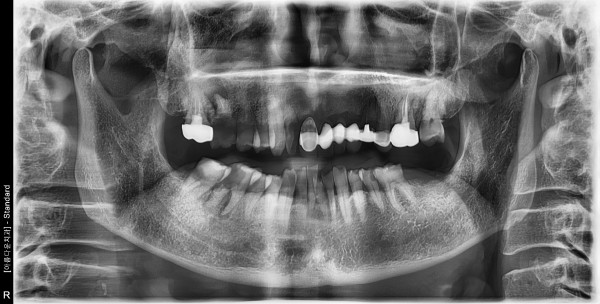

만75세 남성 임플란트